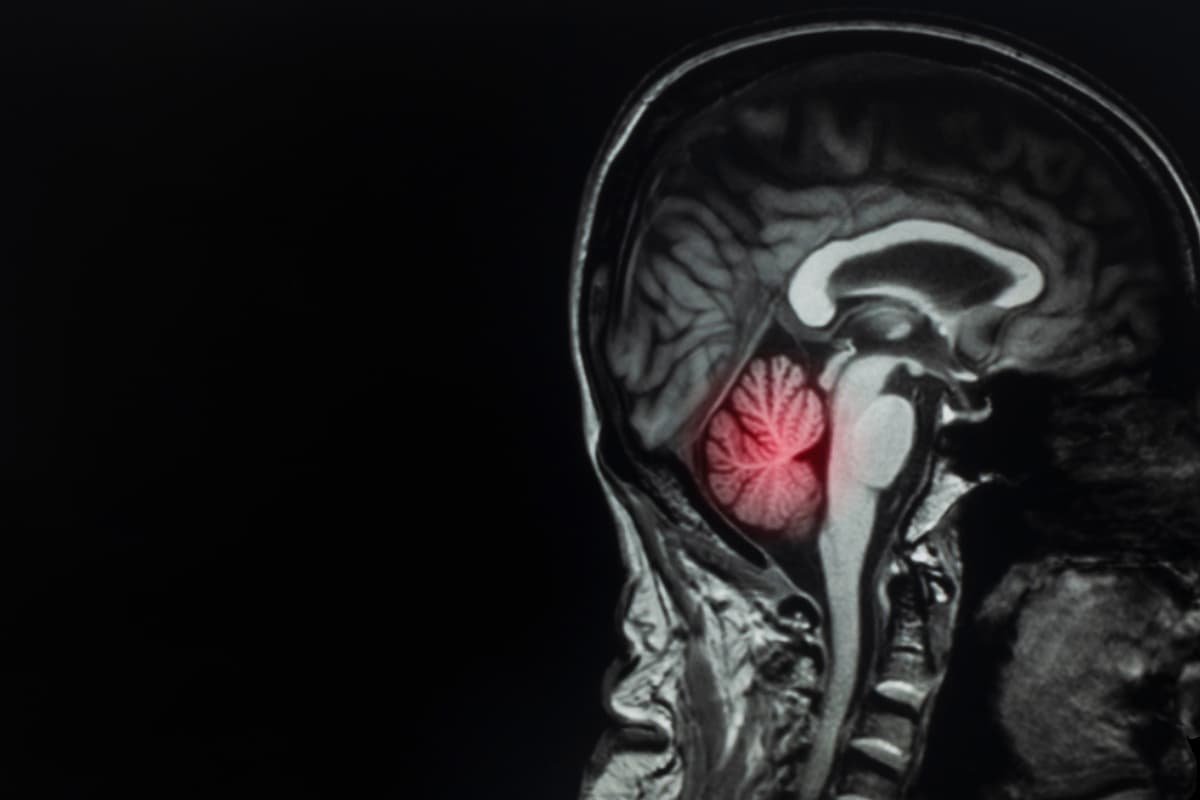

Dagmar, quien es parte de la orquesta sinfónica de la Isla de Wight, al sur de Inglaterra, fue diagnosticada con un tumor cerebral de crecimiento lento hace más de siete años. Sin embargo, el año pasado los doctores se percataron de que estaba creciendo rápidamente y con más agresividad por lo que la violinista decidió removerlo.

La cirugía, realizada en el hospital King's College de Londres, tenía como finalidad abrir la cabeza de Turner para extirpar la masa que se había alojado en su cerebro y que amenazaba con quitarle la vida.

Esta acción tuvo como objetivo proteger células importantes ubicadas, particularmente, en el lóbulo frontal derecho de su cerebro en donde, además, se controla -entre otras cosas- la coordinación de la mano izquierda, indispensable para que Turner pudiera tocar el violín.